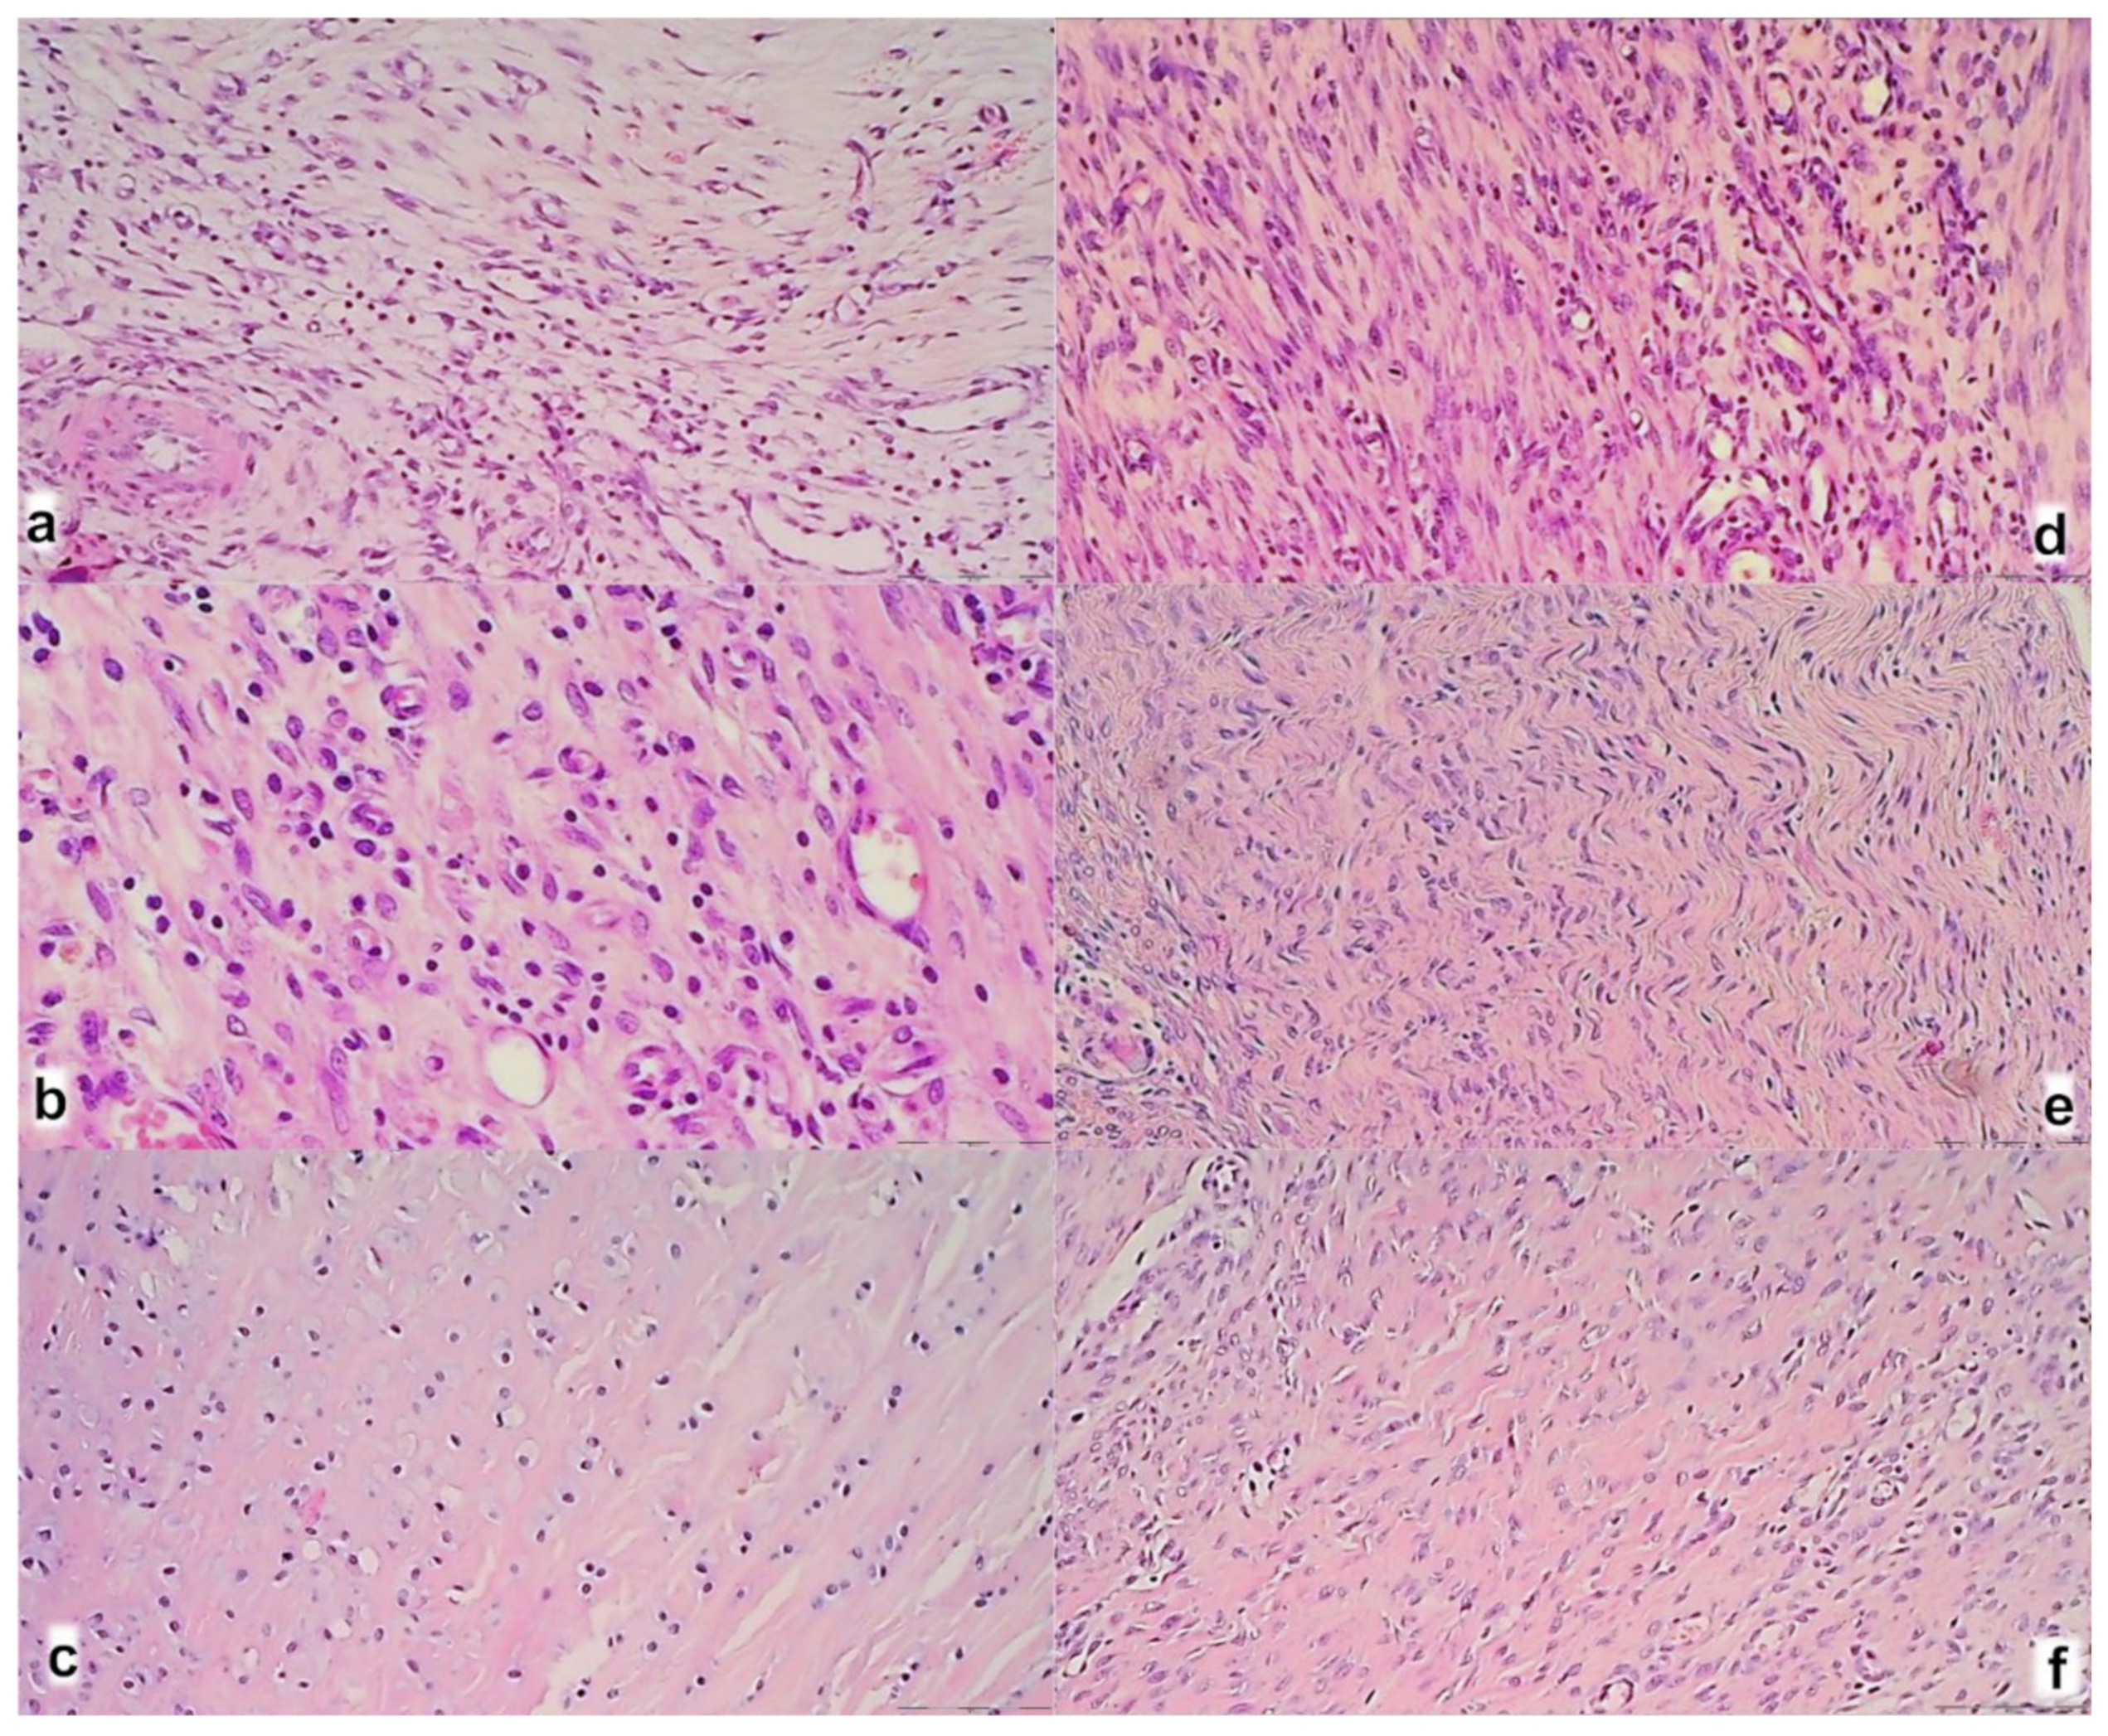

2.7. Microscopy